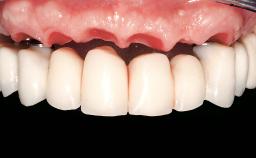

| Case Type | Single-Tooth Space |

| Jaw | Maxilla |

| Area | Posterior |

| Patient's Esthetic Expectations | Low | Medium | High |

| Soft Tissue Anatomy | Intact | Defective | |